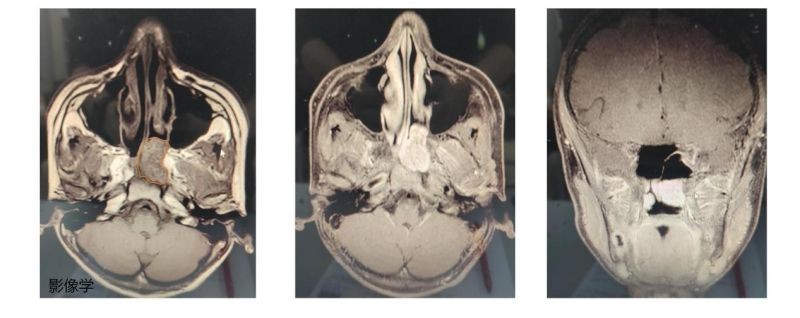

11月19日,13岁的小廖因鼻腔反复出血半年多,到广西壮族自治区南溪山医院耳鼻咽喉头颈外科就诊,当天坐诊的邹攀博士凭借丰富的经验确诊小廖患有鼻咽纤维血管瘤。

耳鼻咽喉头颈外科副主任孔令平介绍,鼻咽纤维血管瘤是一种少见但危险的疾病,常发生于16~25岁男性青年,瘤中含有丰富血管,容易出血,故又名“男性青春期出血性鼻咽血管纤维瘤”。手术需要在狭小的鼻咽腔内操作,因此对手术医生技术和经验的要求很高。尤其是在13岁这样的特殊年龄段,医生需更加谨慎。

小廖确诊后,南溪山医院的医护团队快速为其制定了全面的治疗方案。首先由介入治疗科副主任蒋洪春为小廖进行了数字减影血管造影(DSA)以及上颌动脉及咽升动脉栓塞术,通过导管介入的方法,阻断瘤体责任血管的供血以达到减少术中出血的目的。蒋洪春凭借多年的临床经验和高超的技术,成功完成了这一关键步骤,为接下来的手术奠定了基础。